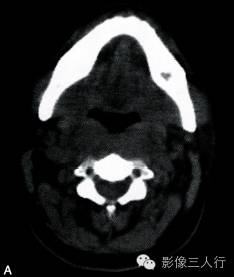

A~C.CT平扫横断面;D~F. CT增强横断面;G. HE×40

双侧甲状腺、颌下腺及咽淋巴环见多发结节融合状软组织影,边界不清,可见包膜,病灶密度欠均匀,内可见线样分隔,未见明显坏死及钙化,双颈各区可见大小不等的淋巴结,边界欠清,密度较均匀(图A~C)。增强横断面(图D~F)扫描双侧甲状腺、颌下腺及咽淋巴环病灶包膜及分隔可见明显强化,双颈淋巴结可见较明显强化。